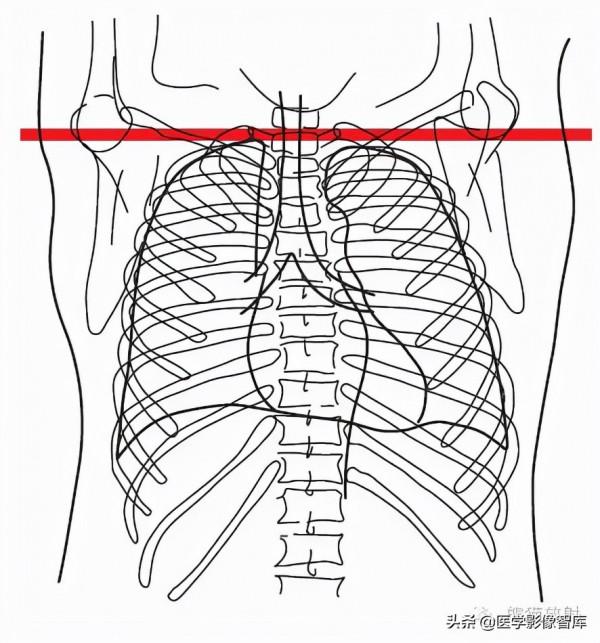

第十一層:四腔心水平